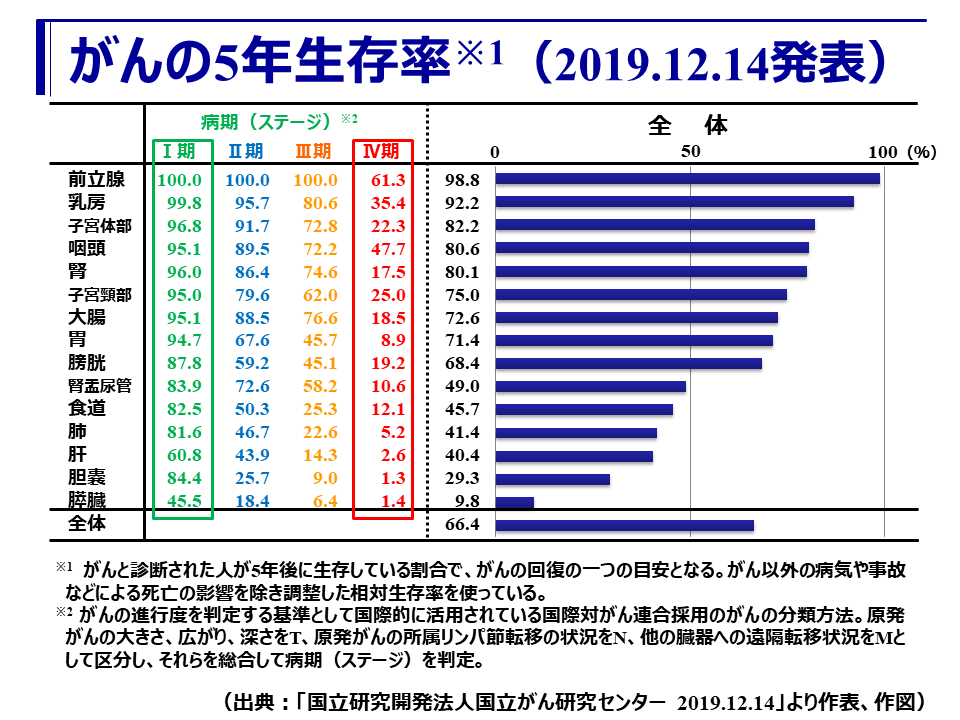

副腎がんの生存率は、診断時の段階や治療に対するがんの反応など、いくつかの要因によって異なります。

副腎がんの生存率は診断時の段階によって異なります。副腎がんは後期段階で診断されることが多いため、全体的な 5 年相対生存率は低くなります。

ただし、副腎がんの生存率には多くの要因が影響しており、まだ転移していない副腎がんの方が生存率ははるかに高くなります。

米国癌協会は、次の統計を使用しています。

- 限局性:がんは副腎を越えて広がっていません。

- 局所:がんが副腎から近くのリンパ節または他の構造に転移しています。

- 遠隔:がんが肺や肝臓など、身体のさらに離れた領域に転移しています。

これらのカテゴリーに基づいて、次のとおりです。

| がんの段階 | 生存率 |

|---|---|

| ローカライズされた | 73% |

| 地域的な | 53% |

| 遠い | 38% |

| すべてのSEERステージを組み合わせたもの | 50% |

これらの数値は、がんが最初に診断されたときのがんの段階にのみ適用されることに注意してください。これらは、年齢、全体的な健康状態、治療に対する反応などの個別の要因を考慮していません。

診断時のがんの段階、人の全体的な健康状態、がんが治療にどの程度反応するかなど、多くの要因が相対生存率に影響します。

副腎がん患者の治療結果には、次のようないくつかの要因が影響します。

- 診断時の年齢:一般に、若いほど治療成績が良好です。

- 全体的な健康状態:全体的な健康状態が良好な人々は、多くの場合、より良い治療結果をもたらします。

- がんの病期:副腎がんが転移しておらず、早期に診断された場合、治療はより成功することがよくあります。

- 治療反応:特定の治療に対するがんの反応は、副腎がん患者の生存率に大きく影響します。

副腎がんは進行性のがんであり、通常は後期になるまで診断されません。副腎がんは早期に診断されれば治癒できる可能性が高くなります。ただし、副腎がんの全生存率は約 50% です。

副腎がんの生存率は、診断時のがんの病期、全体的な健康状態、治療に対するがんの反応など、多くの要因によって決まります。